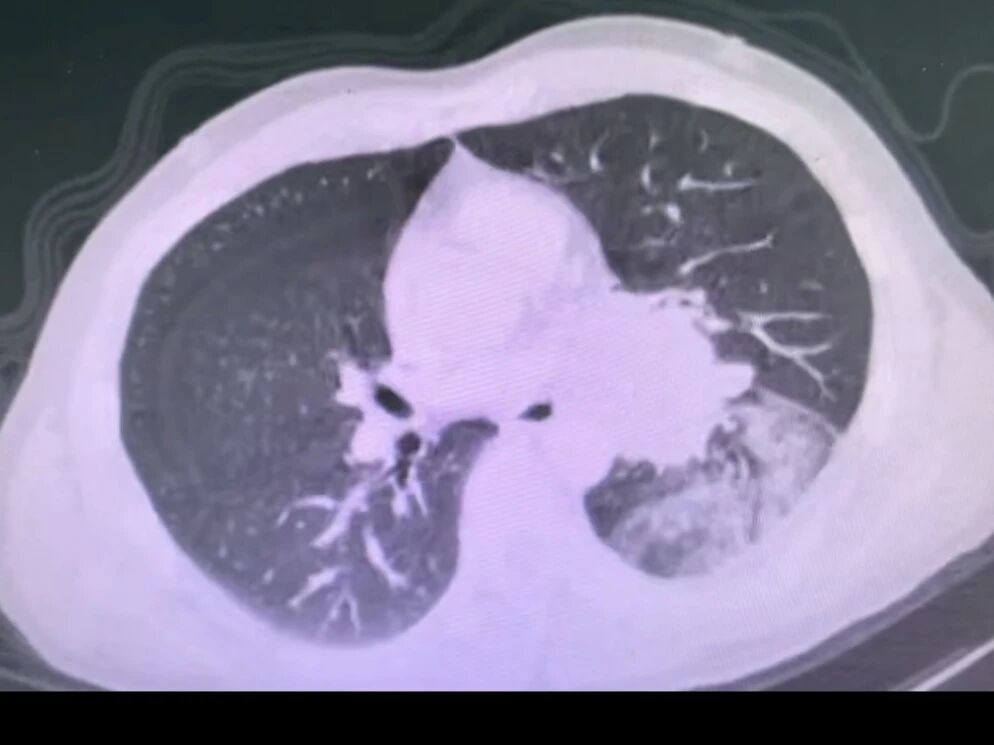

胸部ct提示左肺门巨大占位,包绕肺门主要结构